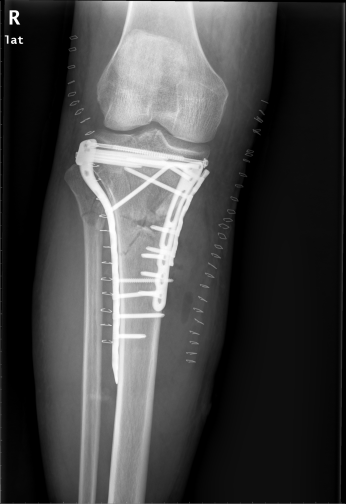

骨折是我们在日常生活中常见的一种疾病,通过手术治疗往往可以达到稳定的固定作用。手术固然重要,但术后功能康复亦不能忽视。小编最近就遇到一位胫骨平台骨折患者,该患者在4个月前发生了车祸导致胫骨平台骨折,并进行切开复位内固定手术治疗。但由于在术后一直畏痛少动,未进行积极地康复治疗,致使患侧膝关节难以像健侧一样伸直,下肢功能急剧下降。为了避免出现以上情况,今天小编就与您分享,胫骨平台骨折术后该如何正确康复。

胫骨平台是膝关节重要的负荷组成部分,也是膝关节创伤中最常见的骨折之一,多发生于强烈的外翻和内翻应力合并轴向载荷时,同时股骨髁对其下胫骨平台有压力和剪切力,可造成劈裂骨折、塌陷骨折或两者兼有。当发生胫骨平台骨折后,需要通过手术切开复位固定,术后要及时进行康复训练,以加快骨折愈合,促进患肢功能恢复。

1. 拍摄膝关节X光片复查,并根据骨折线愈合情况及专业医生建议决定是否开始进行患肢负重练习。